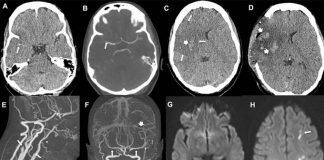

Covid-19 vaccine: Common stroke symptoms must be ‘urgently evaluated’

UCL and UCLH neurologists have published the first clinical observations of patients who experienced an ischaemic stroke, the most common form of stroke, following an Oxford AstraZeneca vaccine.